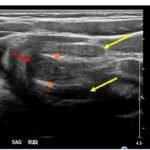

The patient’s abdominal ultrasound revealed intussusception in the right upper abdominal quadrant. The transverse ultrasound view showed a “doughnut sign” (dashed yellow line), telescoping bowel (yellow arrow), and invaginated hyperechoic mesenteric fat with crescent configuration (dashed orange line). The sagittal ultrasound view demonstrated the intussusception formed by the outer recipient bowel loop (yellow arrows), invaginated hyperechoic mesenteric fat (orange asterisks), and telescoping bowel centrally (red arrow).